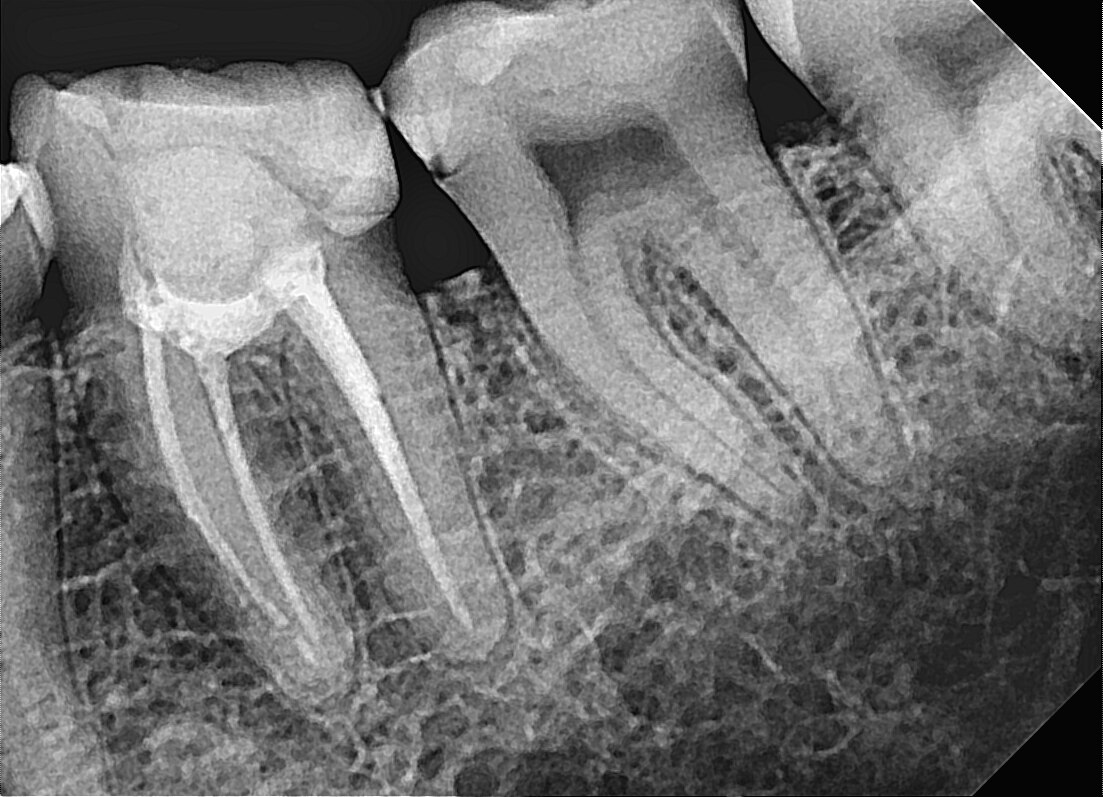

Dentalni radiogrami, poznati i kao zubni rendgenski snimci, predstavljaju naprednu dijagnostičku metodu koja omogućava detaljan uvid u strukturu zuba, vilice i okolnih mekih tkiva. Ova tehnologija omogućava stomatolozima da otkriju probleme koji nisu vidljivi golim okom, poput karijesa ispod plombe, infekcija, cisti i problema sa korenom zuba.

Dentalni rendgenski snimci koriste minimalne doze zračenja kako bi generisali visokoprecizne slike unutrašnje strukture zuba. Digitalni radiogrami dodatno smanjuju izloženost zračenju i omogućavaju stomatolozima da brzo dobiju detaljne slike koje pomažu u tačnoj dijagnostici i planiranju tretmana.

• – Dijagnostiku karijesa, infekcija i cisti

• – Planiranje ortodontskih tretmana i ugradnje implantata

• – Proveru položaja umnjaka i drugih zuba

• – Proveru položaja kanala u korenu radi lečenja zuba

• – Otkrivanje gubitka koštane mase kod parodontalnih oboljenja